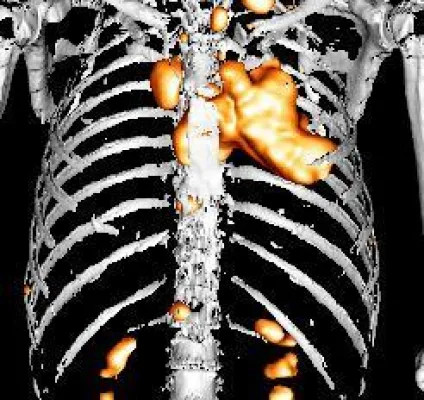

Die fortschrittliche GE VUE Point HD iterative 3D-Rekonstruktion verbessert die Auflösung bei exzellenter Bildqualität. Auch kleine Läsionen können so entdeckt und die quantitative Genauigkeit erhöht werden.